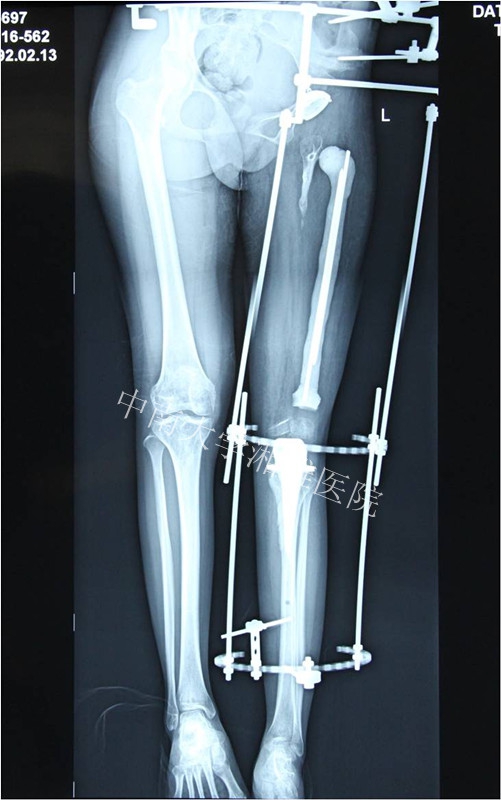

患者,女,21岁。

主诉:左下肢短缩,活动不能21年

出生后8个月出现左股骨中段骨髓炎,在当地医院予以保守治疗,1年后好转。其后出现左大腿停止发育,左下肢短缩,行走活动不能。2012年10月至中南大学湘雅医院门诊求治,摄片发现左股骨未发育,收入住院。

左大腿可见1*2cm²伤口疤痕,无红肿、窦道流脓

左下肢短缩23厘米

左大腿中段无骨质支撑,可反常活动

入院诊断:左股骨骨髓炎后遗股骨发育不良

2013年4月软组织延长术后

2013年6月安装胫骨侧假体,自制股骨骨水泥占位器占位,继续延长